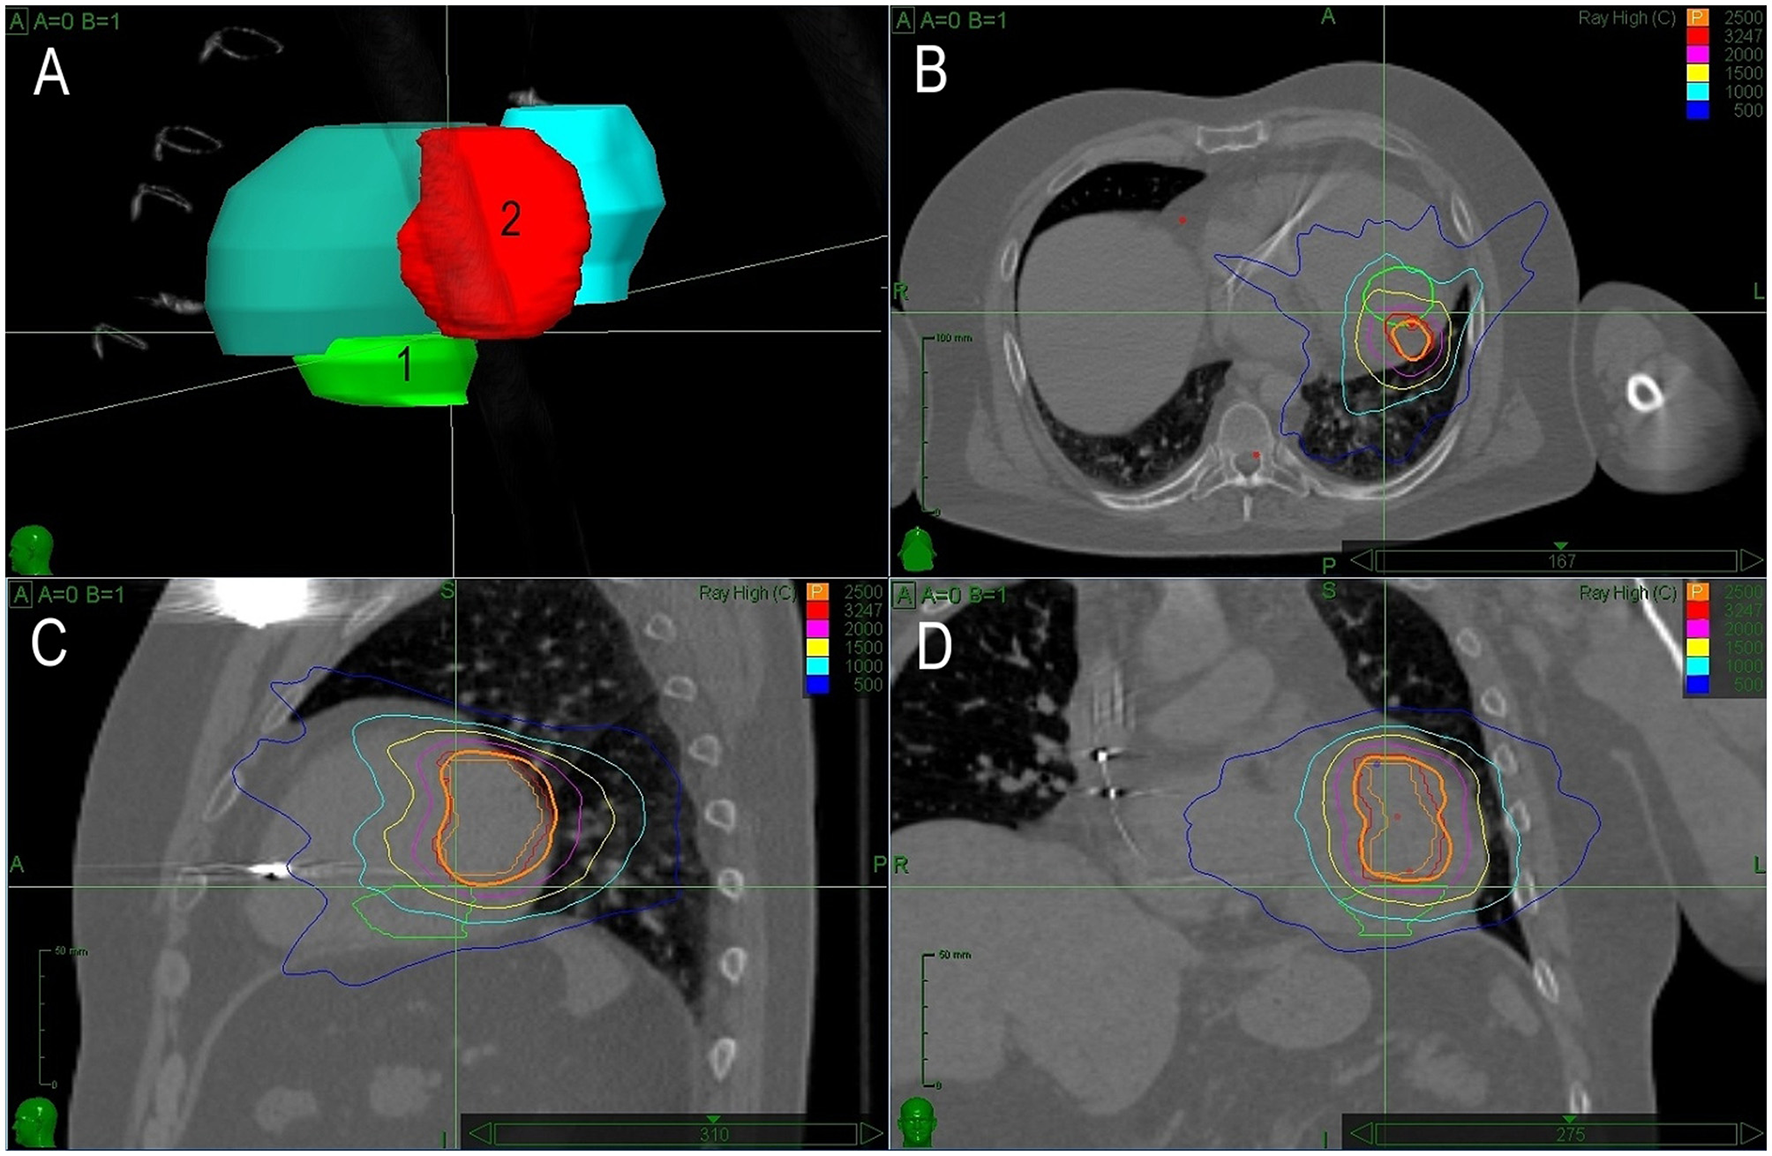

The second case of a patient with cardiac fibroma triggering recurrent VTs of different morphologies was reported after the first successful SBRT in 2017 (10). Briefly, it was a 34-year-old patient diagnosed with an intramyocardial tumor (60 × 40 × 25 mm) located in the inferolateral wall of the left ventricle. The patient presented with several morphologies of VT. The patient underwent exploratory surgery, but the excision of the tumor was impossible for its size. Only far-field signals were recorded above and around the tumor. Empirical epicardial cryoablation around the tumor was performed with transient suppression of VTs. Subsequent electroanatomical mapping and pace mapping identified two regions responsible for two residual clinical VTs. One had a reentrant character with an exit in the lateral wall, which was close to the summit. This VT was non-inducible after catheter ablation. The other VT became incessant and originated in a region between the septum and posteromedial papillary muscle. It had characteristics of focal VT with a source located deep in the wall, adjacent to the tumor. The patient was referred for SBRT. PTV was determined based on tumor location and visual comparison with electroanatomical maps. SBRT was performed with 25 Gy to the 75% isodose line. After the procedure, VT disappeared gradually within 6 months. The patient was without any arrhythmia for the next 22 months. However, the patient remained on amiodarone which had to be stopped due to amiodarone-related thyrotoxicosis. After successful treatment of this condition, the patient was without arrhythmias for the next 10 months. Then, the patient returned with an electrical storm and one morphology of VT. Electrophysiological study induced sustained VT from the anterolateral basal part of the ventricle. Electroanatomical bipolar voltage map showed normal values and pacing revealed slowed conduction in this region. Ablation did not prevent the inducibility of VT due to the deep location of the substrate. The second session of SBRT was planned and conducted based on precise integration of data from electroanatomical mapping and CT. PTV for the second SBRT was applied on the opposite side of the tumor and there was no overlap with the first radiotherapy site. The size of the tumor remained the same. After the second SBRT (25 Gy, PTV 62.2 ml; Figure 2), the patient remained without VTs and did not gain any adverse effects for 22 months.

Figure 2

The treatment plan for Case 2. Description of (A–D) is identical as in Figure 1. In this case, the second planned target volume covers an entirely different region.